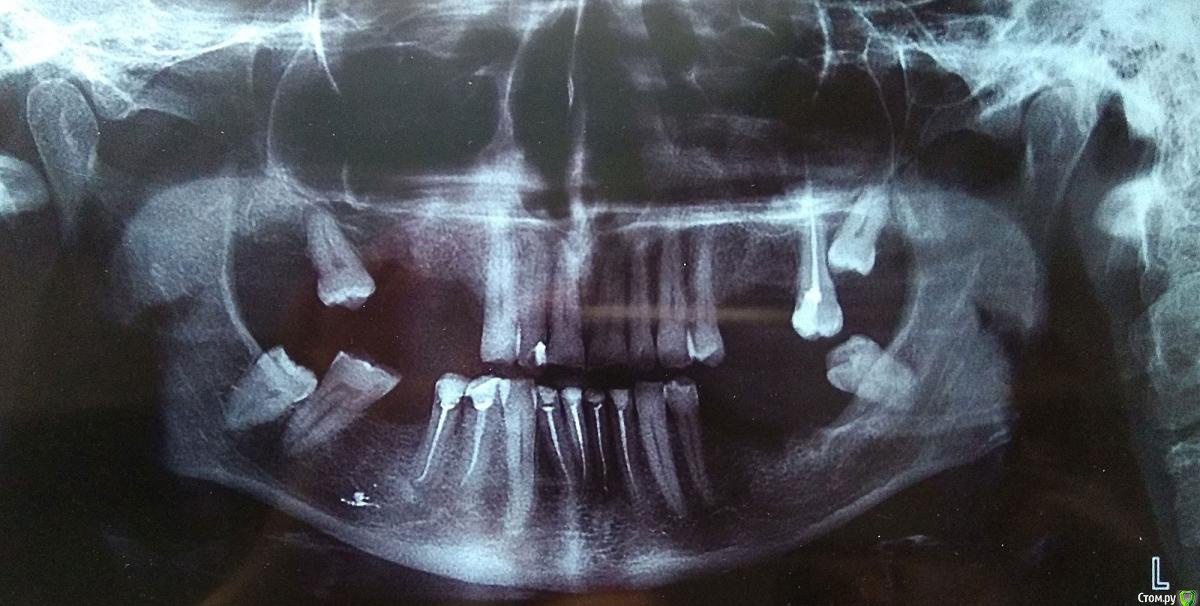

Jonatan Опубликовано 23 октября, 2016 Автор Поделиться Опубликовано 23 октября, 2016 (изменено) Одно и то же снято через стекло и просто на белом листе.Оказывается, послесанационный снимок был (ошиблась). Спасибо. Изменено 23 октября, 2016 пользователем Jonatan Ссылка на комментарий